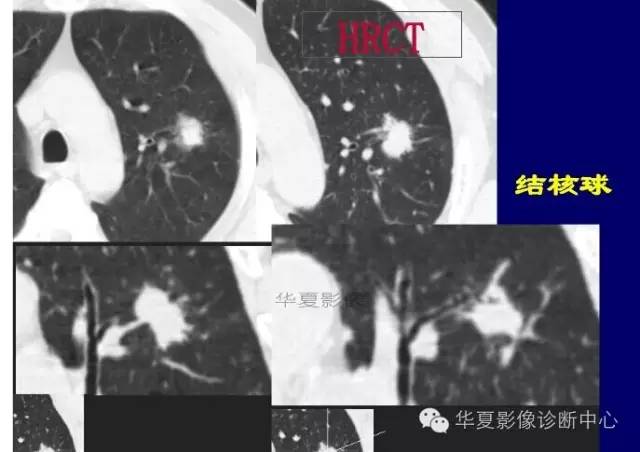

大家仔细看看这个中央不强化的腔内壁

你会发现内壁强化明显,边界清楚

一般这是炎性的脓腔,内层是肉芽肿,明显强化,分界清楚

癌肿的坏死一般是缺血性的,是肿瘤生长速度过快,中央带的血管受挤压,中央供血不足坏死的,一般边界模糊

内有内层强化,不会这么清楚

这是两者坏死的差异

内带强化带,边界清楚

但是这个其实整体看起来不是分叶征

只是一个一个的凸起